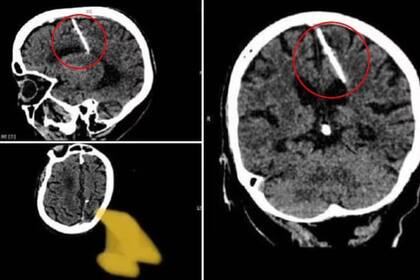

Una mujer de 80 años fue a un centro médico para hacerse una tomografía computarizada de su cerebro. Gracias a ese estudio, cuyo motivo no trascendió, tanto ella como los profesionales que la atendieron descubrieron con gran asombro que tenía insertada, en un sector de su lóbulo parietal izquierdo, una aguja de unos tres centímetros de longitud.

Como poco tiempo después la fontanela se solidificaba, el crimen de la bebé no dejaba pruebas y sus padres no recibían el castigo merecido por la muerte de la pequeña. Pero en este caso, según explica el Departamento de Salud de Sajalín, “la aguja penetró el lóbulo parietal izquierdo pero no tuvo el efecto deseado: la niña sobrevivió”.

Las autoridades de Salud de la isla aseguraron luego que la situación de la paciente no está en peligro con ese elemento instalado en su lóbulo parietal izquierdo, pero está siendo supervisada por personal especializado. El lóbulo parietal izquierdo, según informa el Daily Mail es el sector del cerebro donde se procesa la información sensorial y donde se desarrollan acciones complejas como las matemáticas.